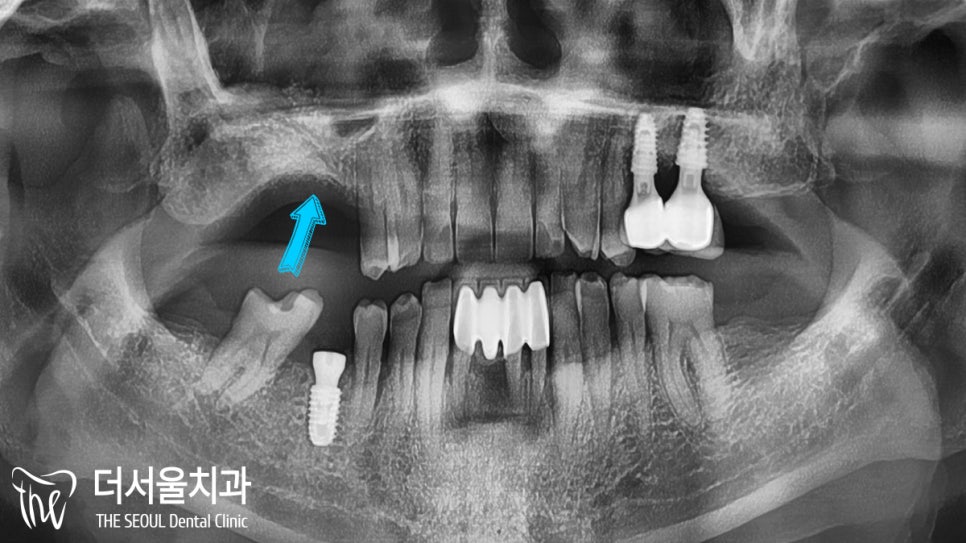

4개월의 시간이 흘렀습니다.

오.. 이제는 뼈가 형성되었네요~

이제 계획했던 대로

상악동거상술 및 골이식을 진행하고

그 뒤로 임플란트 를 심어야 되겠네요.